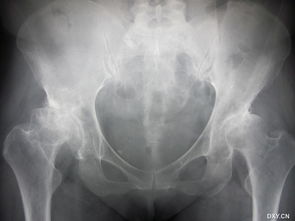

做了人工關(guān)節(jié)置換手術(shù)之后,患者需要在今后漫長的生活中注意多加保護(hù),注意護(hù)理,這樣才能保證人工關(guān)節(jié)的使用壽命。

人工關(guān)節(jié)置換術(shù) 后的注意事項(xiàng) 1、減輕體重: 髖、膝關(guān)節(jié)承受的力量大部分是人體的重力,所以減輕體重就能減少對(duì)關(guān)節(jié)的壓力。術(shù)后要合理安排飲食,保持體重控制在正常范圍內(nèi),以減輕對(duì)關(guān)節(jié)的磨損。

2、保持正常的肢體對(duì)線和步態(tài): 正常的肢體對(duì)線和步態(tài)能夠使關(guān)節(jié)面保持足夠的接觸面積,均勻受力,這樣就不至于使力量過于集中在某些區(qū)域,加重磨損。所以在站立時(shí),必須保證腿伸直,走路時(shí)要邁開大步,不能蜷著腿走路。

3、增強(qiáng)肌肉力量: 良好的肌力不僅能使患者活動(dòng)自如,增強(qiáng)運(yùn)動(dòng)協(xié)調(diào)性和姿勢(shì)反射靈敏性,而且能在一定程度上減少關(guān)節(jié)受力,平時(shí)要堅(jiān)持鍛煉患肢肌力。 4、避免大量和高難度活動(dòng):做了關(guān)節(jié)置換手術(shù)的病人,應(yīng)該減少活動(dòng)量,尤其是老年患者,通常關(guān)節(jié)置換2-3個(gè)月后能夠不需要扶拐行走,您可以從事大多數(shù)日?;顒?dòng),可以散步,騎車,跳舞,游泳。

還可以練練氣功,打打太極拳,避免長時(shí)間行走、站立,避免蹲起動(dòng)作。另外,爬山,爬樓梯,跑步有損于人工關(guān)節(jié),建議不做或少做。

您可以扛些重物,但扛太重的東西,尤其是在上下樓或者走坡道時(shí),就不合適了。5、防治骨質(zhì)疏松:前面說過,疏松的骨質(zhì)不利于假體的固定,支持力也弱,長期會(huì)發(fā)生假體的松動(dòng)和下陷,所以要從飲食、藥物和鍛煉三方面防治骨質(zhì)疏松 ,延長假體壽命。

總之, 關(guān)節(jié)置換手術(shù)后需要注意方方面面的問題,才能最大可能的延長關(guān)節(jié)的壽命。